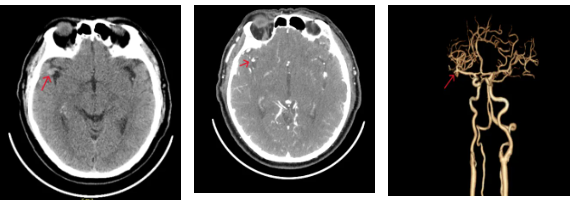

头颅CT及CTA:

右侧大脑中动脉M2段起始部稍高密度结节

头颅MRI:

右侧大脑中动脉M2起始部异常信号结节,考虑动脉瘤